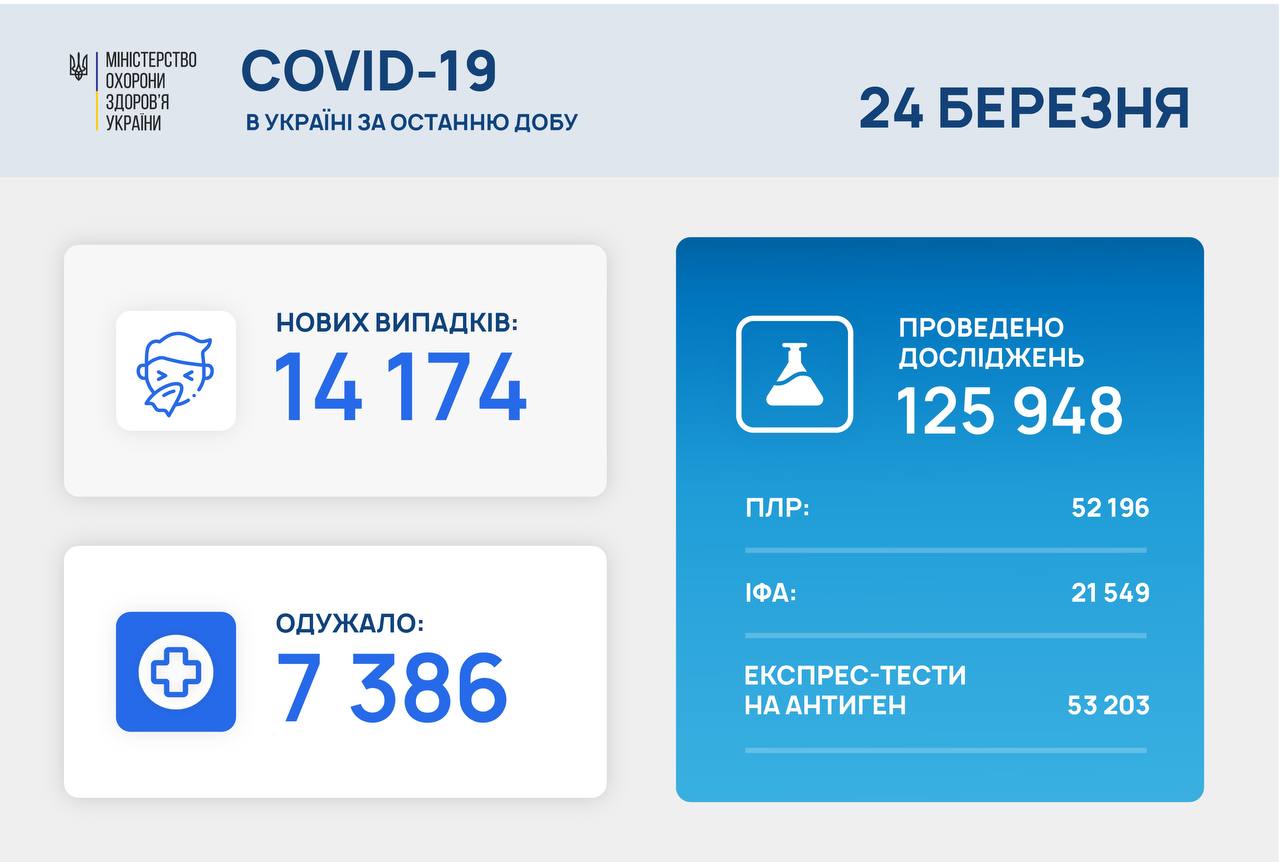

МОЗ: Уперше з початку пандемії було зроблено понад 100 тисяч ПЛР-досліджень за добу